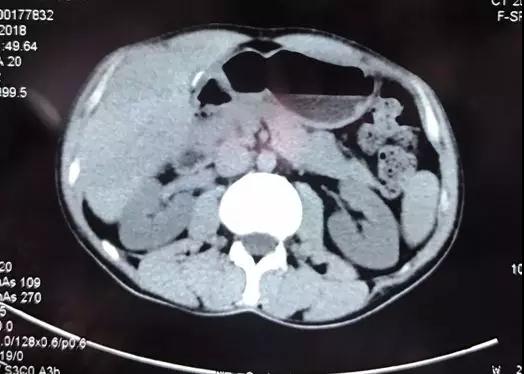

大约一个月前,扎西大夫在群里发了几张CT照片,这是一名反复发作胰腺炎的病人,当地的放射科诊断是“胆总管结石”。由于胆管结石导致的胆源性胰腺炎反复发作,当地大夫考虑第二天为病人做ERCP取石手术。

乍一看,片子上结石的位置好像是在胆管走行区域。但我盯着片子,仔细看过后发现:不是胆管结石,而是胰管结石。在胰头区域,胆管和胰管靠的很近,很容易看走眼。但正所谓“失之毫厘,谬之千里”,如果这个病人真的接受ERCP手术,按照胆管结石处理可就糟了!